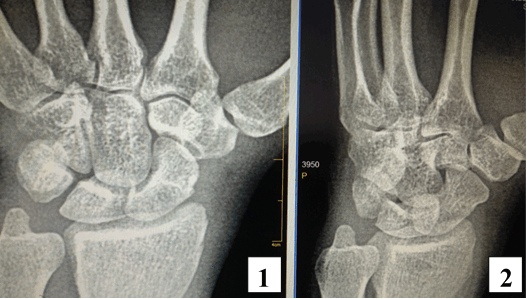

По результату прицельной рентгенограммы правого запястья (рис. 1) достоверных характерных признаков патологических изменений костей правого запястья выявлено не было [1].

Рис. 1. Рентгенография правой кисти: 1 – прямая проекция; 2 – косая (3\4) проекция. Прослеживаются на всем протяжении кости запястья, их взаимоположение удовлетворительное, признаков переломов, или дефектов костной ткани не выявлено